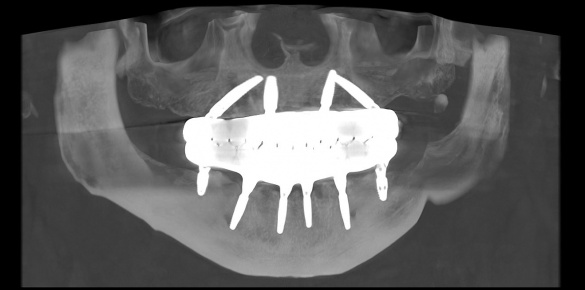

Стоматолог пропонує бійцям весь пакет імплантації, нарощування кісткової тканини, анестезіологічний та медичний супровід, та виготовлення тимчасових коронок для первинної реабілітації. Це все безкоштовно.

Питання виготовлення постійних коронок через 6-12 місяців в процесі вирішення.